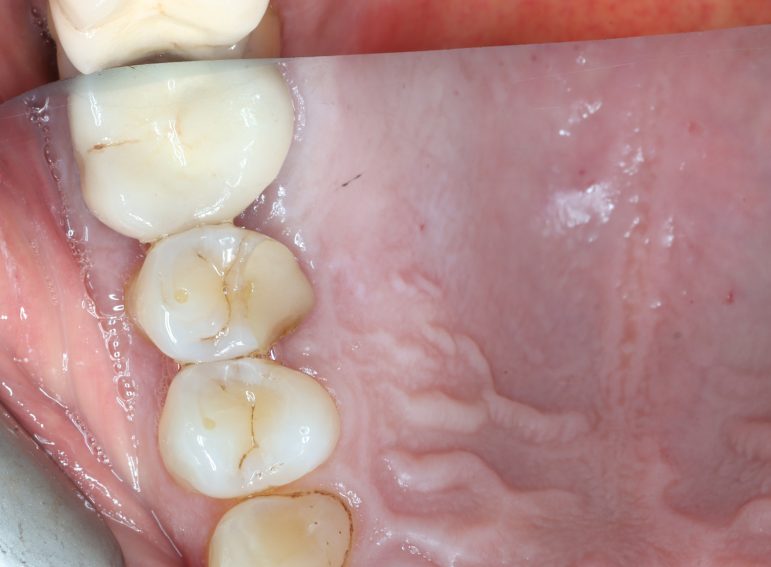

Case 6 – Periodontics

Crown lengthening Surgery on a premolar